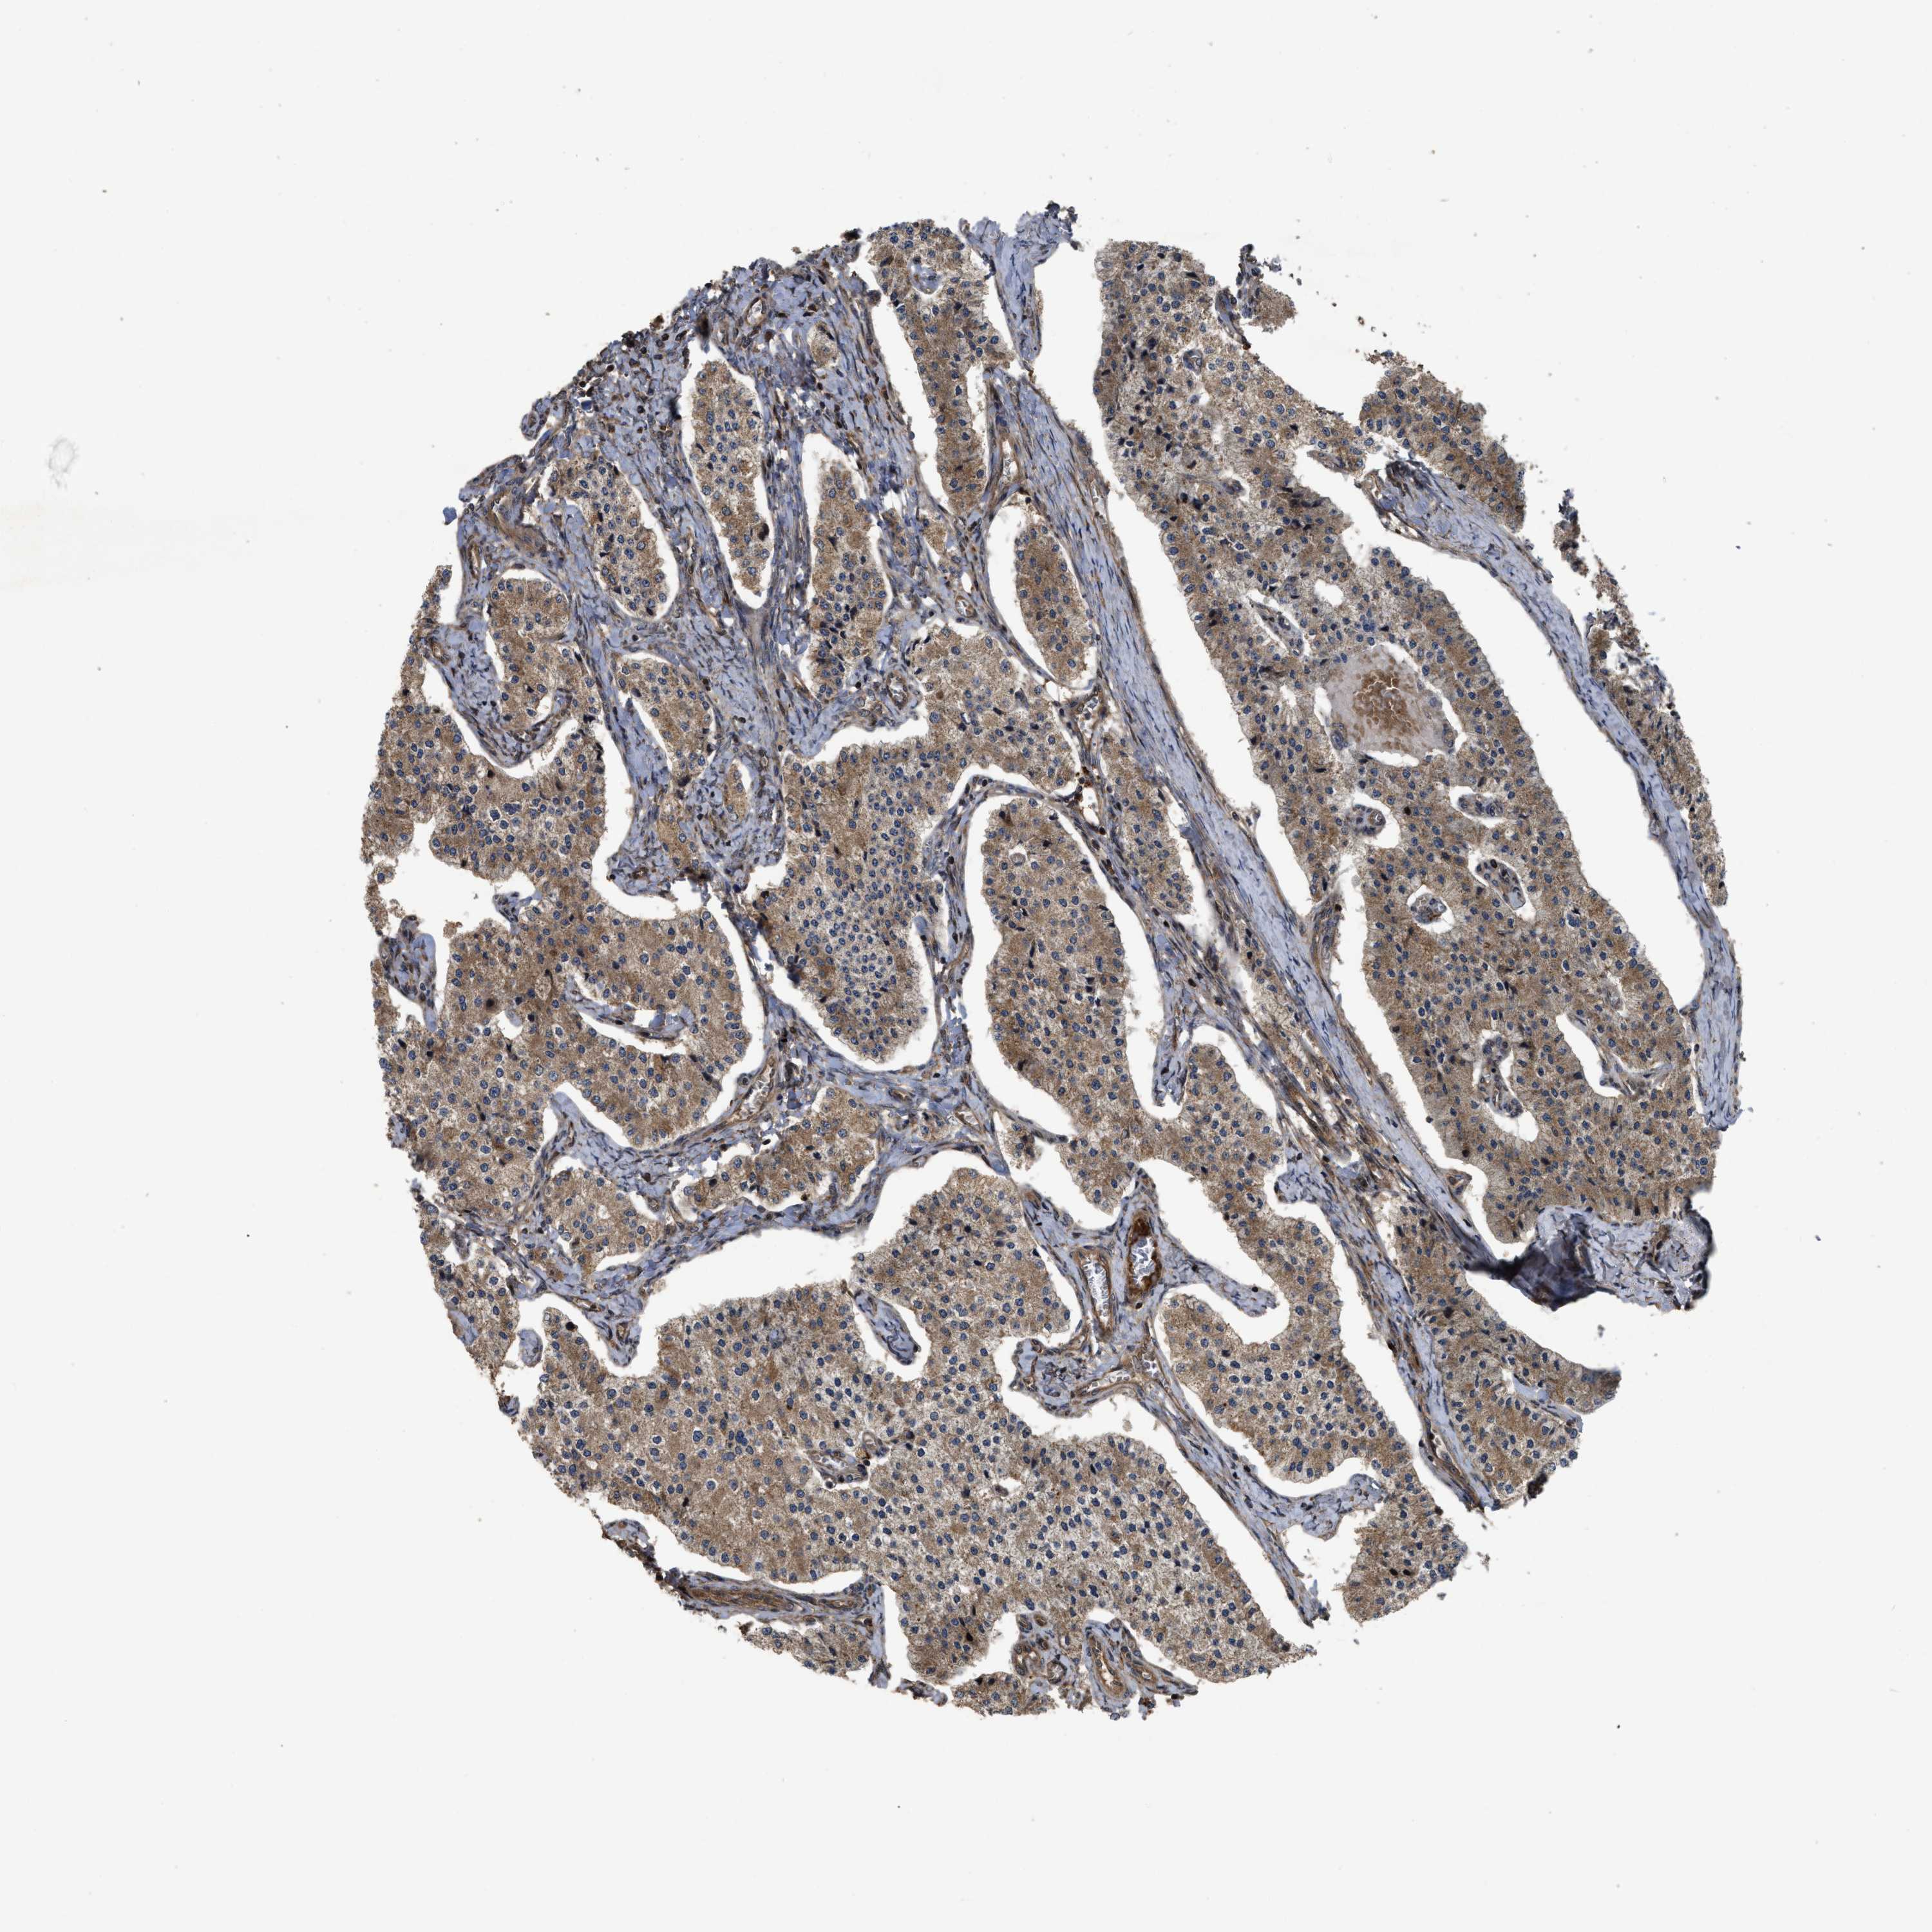

CARCINOID - Protein expressioni

A mouse-over function shows sample information and annotation data. Click on an image to view it in a full screen mode. Samples can be filtered based on level of antibody staining by selecting one or several of the following categories: high, medium, low and not detected. The assay and annotation is described here.

Antibody stainingi

Antibody staining in the annotated cell types in the current human tissue is reported as not detected, low, medium, or high, based on conventional immunohistochemistry profiling in selected tissues. This score is based on the combination of the staining intensity and fraction of stained cells.

Each image is clickable and will lead to virtual microscopy that enables deeper exploration of all samples and also displays staining intensity scores, fraction scores and subcellular localization as well as patient and tissue information for each sample.

Antibody HPA018434

Staining

High

Medium

Low

Not detected

Intensity

Strong

Moderate

Weak

Negative

Quantity

>75%

75%-25%

<25%

None

Location

Nuclear

Cytoplasmic/membranous

Cytoplasmic/membranous,nuclear

Carcinoid, malignant, NOS

Carcinoma, NOS